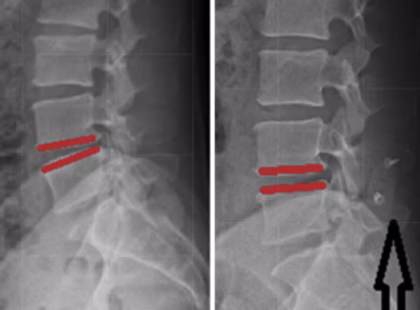

What is the Coflex Procedure?

This minimally invasive procedure is done via a 1-2 inch incision. It is done in conjunction with a lumbar laminectomy, which is a procedure where we remove the arthritis that is “choking” the lumbar nerves. Patients are under full anesthesia and go home the same day. It usually takes less than 60 minutes.

The Coflex procedure is used to treat low back and hip pain that may also radiate into the buttocks, posterior thighs, and lower legs. The procedure is done in the lumbar spine and can be used to treat spinal stenosis, which is a very common condition.